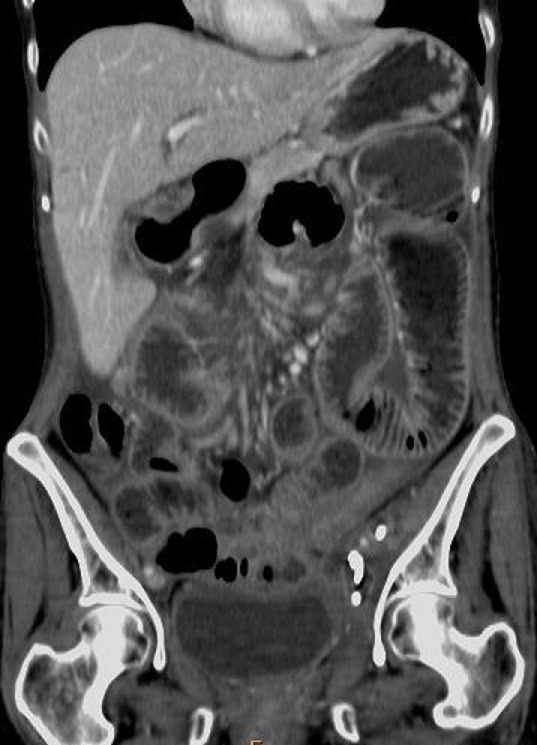

Tomografía Computarizada:

Con sensibilidad y especificidad próximas al 100%, es la técnica inicial de elección ante la sospecha de una obstruccion intestinal. Ante la sospecha firme de obstruccion intestinal, realiza un diagnóstico más preciso, aporta más información adicional y evita retrasos en el diagnóstico.

Hallazgos:

- Distensión proximal a la obstrucción mayor de 3,5 cm en el intestino delgado y mayor de 5 cm en el colon con colapso de asas distales junto con la identificación, siempre que sea posible, de la zona del cambio de calibre (zona de transición), lo que nos permite realizar con mayor seguridad el diagnóstico.

- Si se observan asas dilatadas, independientemente del grado, si no hay colapso de asas distales, el diagnóstico más probable es un íleo paralítico.

- Engrosamiento mural de asas.

- Afectación de la grasa mesentérica adyacente, lo cual se produce en caso más evolucionados.

- Nivel de la obstrucción: determinado por la zona de cambio de calibre.

- En caso de obstrucción de un asa de colon existirá dilatación del colon proximal. Si la válvula es incompetente existirá también, además, dilatación de intestino delgado.

- Signos de isquemia intestinal.

- Hernia estrangulada (asa intestinal con signos de isquemia en el interior de un saco herniario).

COMPRESIÓN EXTRÍNSECA.

Secundario a efecto masa ejercido por procesos extraluminales de etiología muy variada. Lo más frecuente la carcinomatosis peritoneal. Procesos inflamatorios secundarios a apendicitis o diverticulitis son más raros.